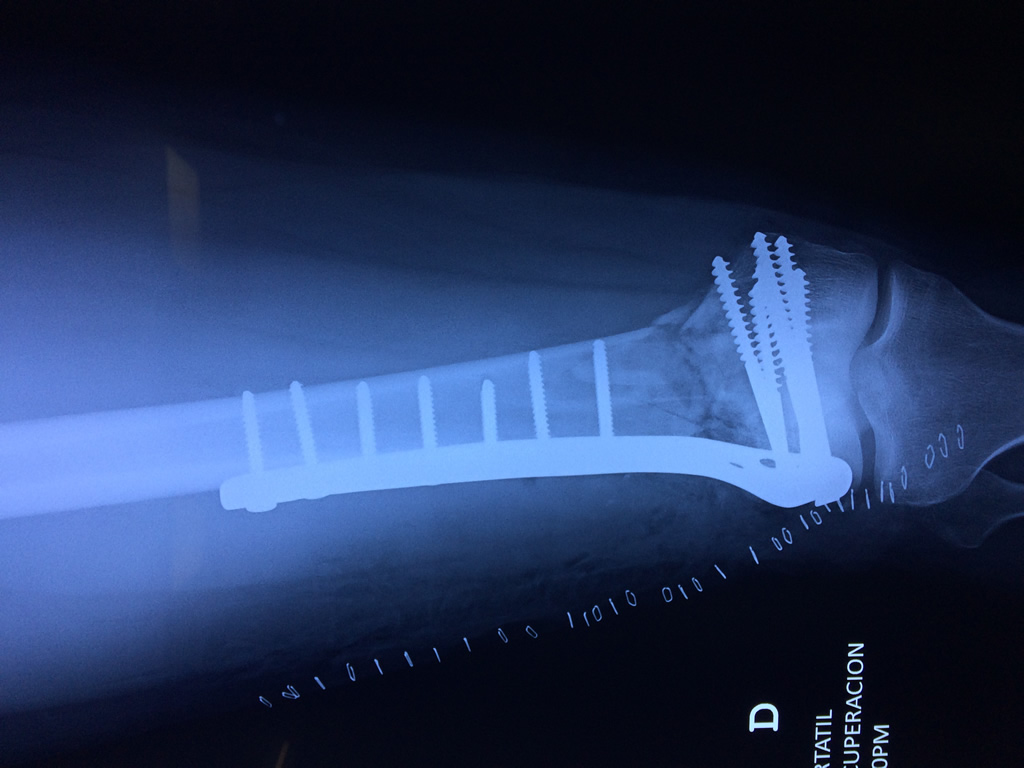

Cirugías de Húmero - Fémur

El fémur es el hueso del muslo, el segundo segmento del miembro inferior. Es el hueso más largo, fuerte y voluminoso del cuerpo humano.